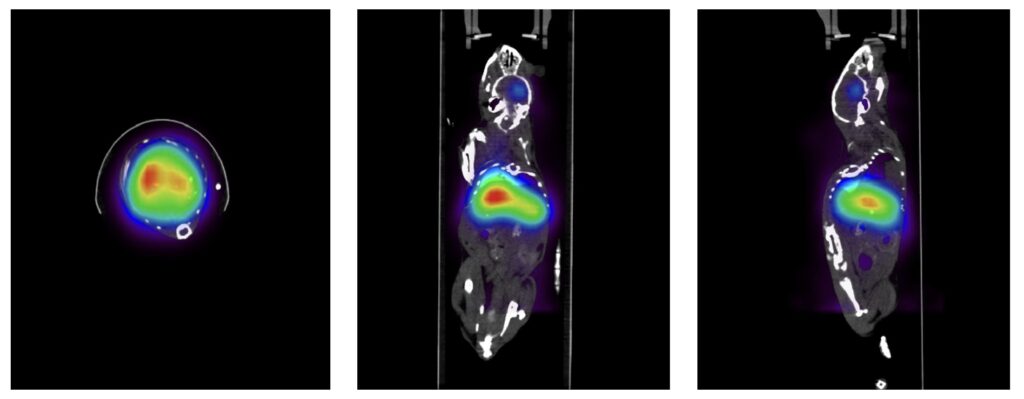

The Alpha-SPECT mini is a high-performance SPECT imaging system for preclinical research (mice and rats). It features high performance CZT sensors providing an unparalleled energy resolution. The scanner offers an ultra-wide stationary FOV to allow for TRU whole-body dynamic scanning of both mice and rats. This allows for imaging up to 4 mice simultaneously. This is a first in its class SPECT scanner with exceptional sensitivity, resolution, and many unique features.

What and Why: Alpha-SPECT Mini™